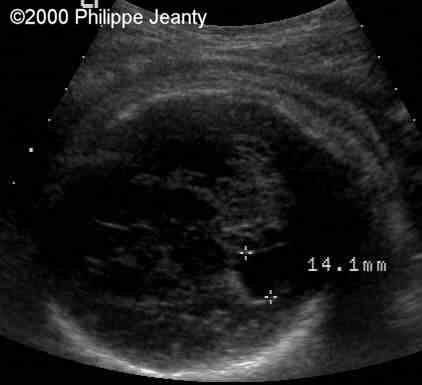

The atrium was distended at 14 mm.

case0020-7

The head with measurements of the biparietal diameter and occipitofrontal diameter. Note that the BPD is well below the 5th percentile but not as far as the limbs

case0020-8